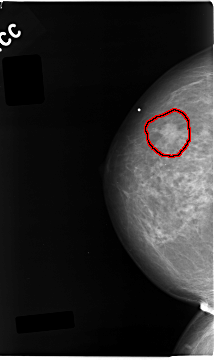

C_0043_1.RIGHT_CC

FILE: C_0043_1.RIGHT_CC.OVERLAY

TOTAL_ABNORMALITIES 1

ABNORMALITY 1

LESION_TYPE MASS SHAPE IRREGULAR MARGINS MICROLOBULATED

ASSESSMENT 5

SUBTLETY 5

PATHOLOGY MALIGNANT

TOTAL_OUTLINES 1

BOUNDARY